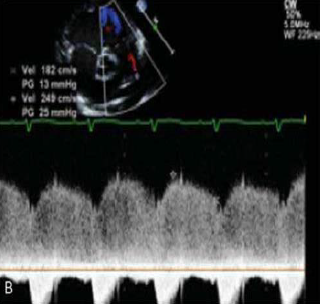

Ao realizar o ecocardiograma de um paciente de 8 meses de vida, evidencia-se apenas canal arterial pérvio conforme ilustrado na seguinte figura. Os sintais vitais do paciente são FC 110bpm PA 85x40 FR 48irpm. Qual é a estimativa da pressão da artéria pulmonar?